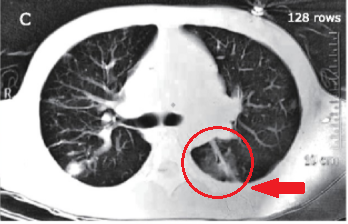

(第三次胸部CT)

这根细长的东西到底是什么呢?没有人知道。

但回顾患者以前的胸部CT,应该是一开始就有的,只不过之前它周围病灶太多,看不清晰,现在病灶少了一些,而且还做了三维重建,看起来就清晰一些了,能认出是一根细长的阴影,这肯定不是患者体内原本就有的,也不会是普通的感染痕迹,从来没有见过细菌或者病毒造成的感染能如此规整(一条直线型)。

问题是,肺里面为什么会有这个细长型的阴影呢,看起来像是一根牙签啊,一根大号牙签,比如说烧烤店里面那些羊肉串、牛肉串的竹签?

由于竹签本身不容易在CT上显影,因为密度不够高,如果是铁签,一开始就会发现了。现在之所以能发现竹签的踪影,应该是竹签周围有一圈炎症,炎症显影了,带着竹签的痕迹显出来(备注:请放射科的老师指正)。

也正是由于这个竹签一直留在胸腔、肺内,所以才会导致反反复复的感染,反复炎症,也有脓肿形成,从三维重建来看,竹签直接刺入了左肺动脉,时间长了就会影响了右心脏,导致右心符合增高,继而出现右心衰竭。所以患者会有胃肠道淤血表现,有胃口不好、腹胀等。

这根竹签直接刺入了左肺动脉,所以一直有炎症、感染,因为竹签本身是不干净的,附带有病原微生物,所以反复引起脓肿,表现类似肺结核。

然后这个患者的表现也是符合的,因为竹签啊,这根竹签模拟了引流淋巴管炎的情况,两端还有脓肿病灶,看起来真的很像原发型肺结核,所以为什么几家医院都会以为是肺结核。